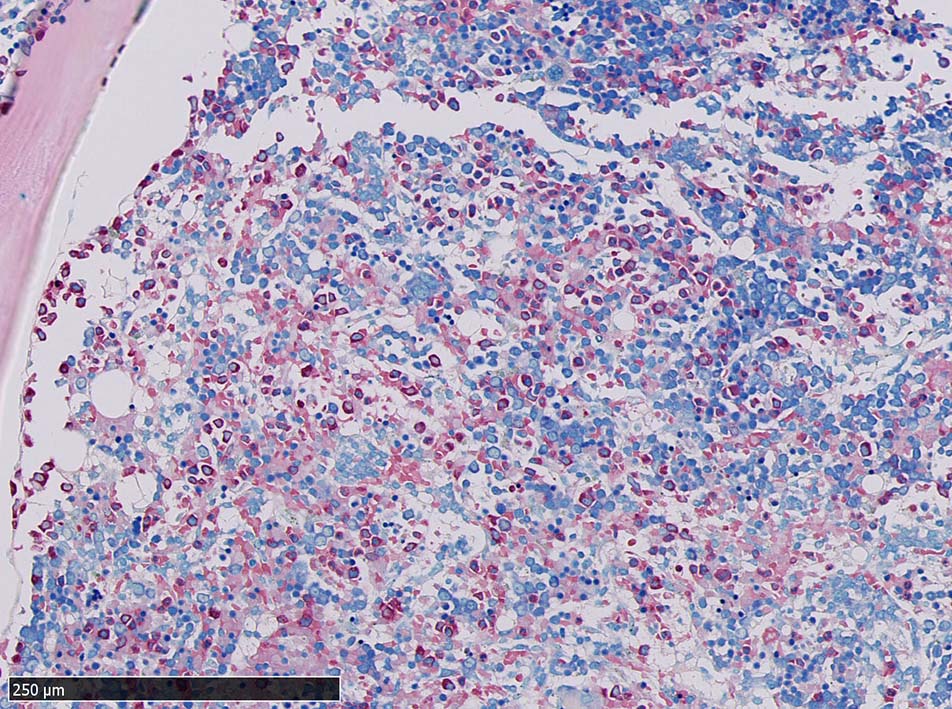

肝臓  サムネイルのクリックで大きな画像が見られます.

肝針生検組織; 類洞に細胞浸潤が認められ, 非浸潤部との境界がぼんやりと認められる. 類洞と異なり, グリソン鞘は腫瘍細胞の浸潤が乏しいか, ほとんど認められない.

骨髄への腫瘍細胞浸潤はintertrabecular patternで, 腫瘍細胞は小集簇巣を形成して散在性に認められた. HE, ASD-Giemsaのみでの浸潤, 増殖の確定はなかなか難しいようです.

ASD-GiemsaではASDに染まらない(陰性の)あやしい細胞塊があるように見える. 細胞小塊はCD3陽性.